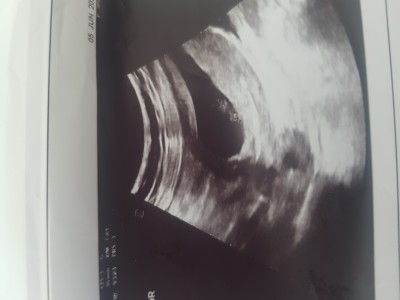

imageplasentanın konumu nerde ise ona gore cinsiyet tahmini yapılıyormuş ben pek anlamadim anlayan varsa bu teorilerden yazabilir mi acaba . Tatlı bir merak her şeyden önce Rabbim sağlık versin tüm hamilelere ve bebislerimize :)

Gebelik haftası 7

7. Haftada plesanta ayırt edilemicek kadar küçüktür ve yeni oluşmaya baslamistir konumuna doktor bile surda diyemez. Bu haftalarda bebeğin eşi yolk sactir. Ramsi teoriside %50lik payı olan bı teoridir. E normalde de zaten %50 kız %50 erkek olma ihtimali var bu teorilere kendinizi kaptırmayın doktorlar bile ciddiye almıyor